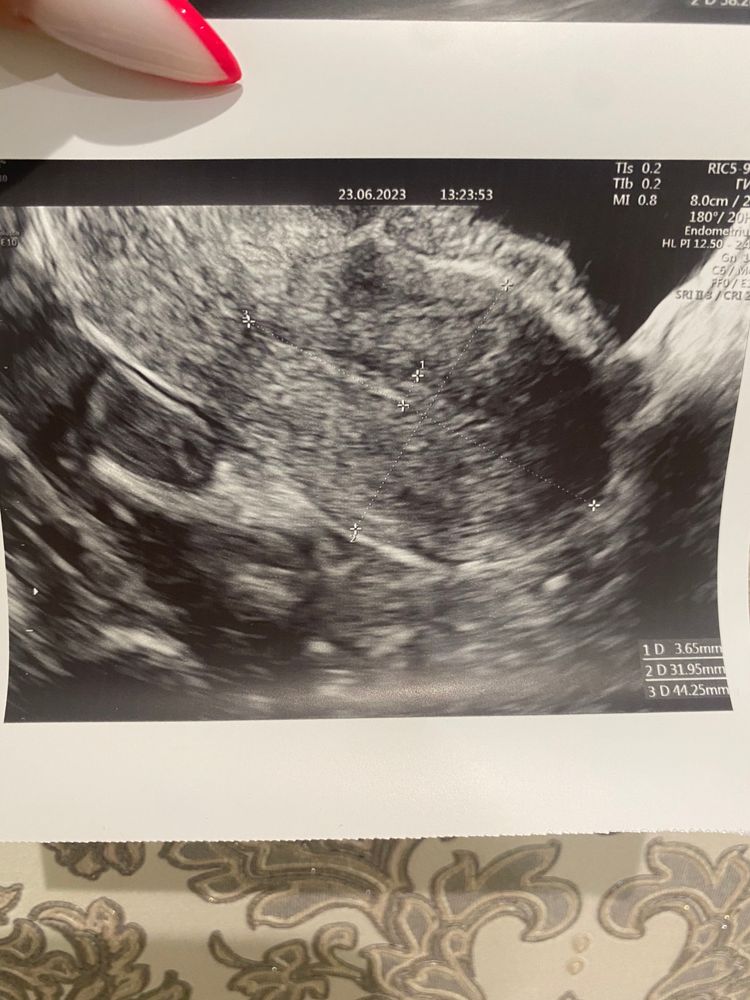

Девочки , подскажите пожалуйста кто разбирается в узи

Да нет никаких кист, это доминантный фолликул. Размер 19х17. Нормальный преовуляторный фолик. У меня таких фоток тьма, желтое тело вообще по другому выглядит

Виктория, думаю просто когда неочевидно они только предполагают. Сказано фоллик должен быть идеально круглый - значит если не круглый, то ЖТ) почему киста только не поняла, размер то нормальный)

Это не жёлтое тело. Это дф. Отслеживали овуляцию по УЗИ несколько месяцев и жёлтое тело оно конечно совсем другое.

По-моему у вас фолликулярная киста, судя по узи яичника и по эндометрию

Девочки че то с мамой поговорила и за переживала климакс в 36 лет у неё тип начался( УЗИ после бхб. Киста, эндометриоз?